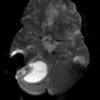

U nguyên bào mạch máu

» Thông tin: Nam giới – 25 tuổi.

» Lâm sàng: Đau đầu + Nôn + Rối loạn thăng bằng.